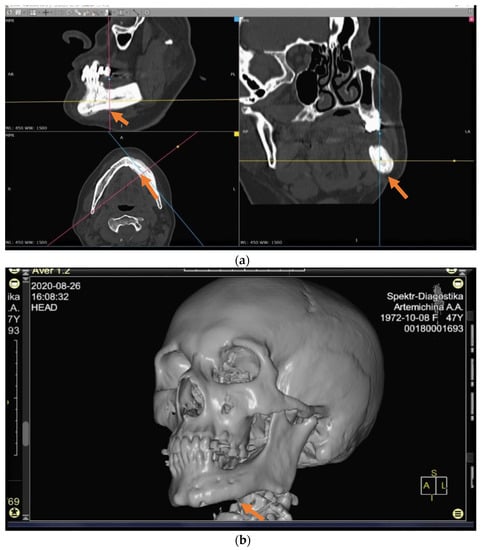

In total, 82 patients were interviewed of which 39 (47.6%) patients were in the control group and the main group included 43 patients who (52.4%) underwent radical surgical treatment (Figure 1a–d). The mean age of the patients in both groups was 66.8 ± 10.03 years. As regards the localization of the primary site of cancer, patients with a history of malignant neoplasm (MN) of the prostate prevailed, followed by MN of the breast (Table 1 and Table 2).

The patients in the main group (43 subjects) underwent segmental resection of the jaw after preoperative preparation (Figure 2 and Figure 3a,b).

An analysis of the results obtained from the Numeric Pain Rating Scale demonstrated that the mean pain intensity before treatment was 8.9 points in the control group, and 9.7 in the main group (Figure 4). These values are indicative of “unbearable pain.” After treatment (30 days), the pain score in the control group decreased and amounted to 4.1; this is evidence of the persistence of “moderate pain” in the patients. In patients who underwent segmental jaw resection (Figure 5a,b and Figure 6), the mean pain intensity was 0.5. There was no relationship with gender, but there was a direct relationship between the intensity of the pain and the stage of the process (CI = 95%).

Figure 1. (ad) Patient A: 47-year-old female. DS: Medication-related osteonecrosis of the jaw (the left side). Surgical treatment: Resection of the lower jaw on the left (9 September 2018).

Figure 3. (a,b) CT scan before operation (26 April 2018).